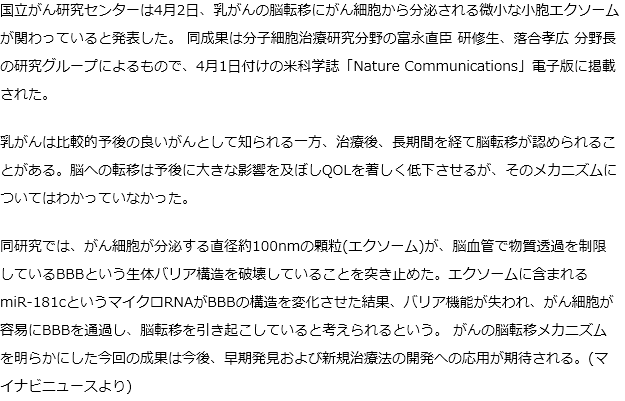

国がん 乳がんの脳転移のメカニズムを解明 がん細胞の分泌物が関係

卵巣がんの治療を困難にする腹膜播種性転移のメカニズムを世界に先駆け